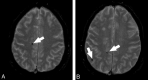

Fig 1.

MR axial images that demonstrate the presence of CMBs. The white arrows indicate the CMBs.